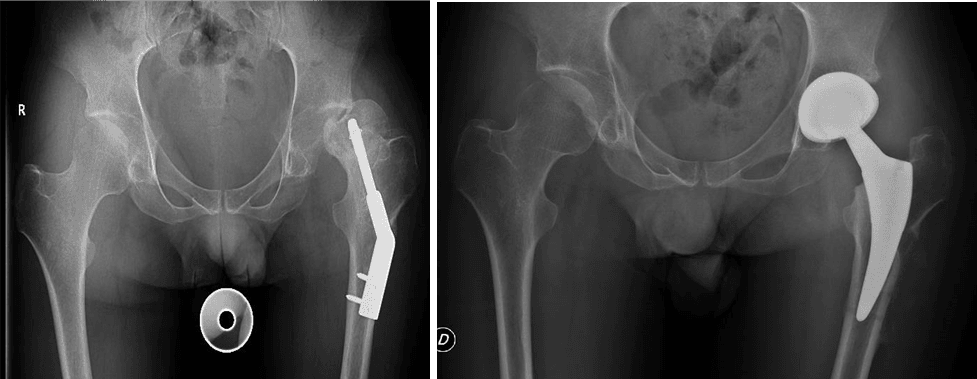

L’intervento di artroprotesi d’anca prevede la sostituzione dell’articolazione dell’anca mediante l’impianto di componenti protesiche in leghe metalliche, come il titanio, accoppiati a materiali plastici (polietilene di ultima generazione) e/o ceramiche. Questo processo include la sostituzione del femore prossimale (testa e collo) e il rivestimento della cavità acetabolare del bacino. L’obiettivo principale di questa procedura è ripristinare un’articolazione stabile e funzionale, migliorando significativamente la capacità di movimento del paziente, alleviando il dolore e migliorando la qualità della vita.

Esistono diverse vie d’accesso chirurgiche per l’artroplastica d’anca; quelle preferite nel nostro centro, a seconda delle caratteristiche del paziente, sono la via postero-laterale e la via anteriore. Ognuna di queste vie ha caratteristiche e vantaggi specifici, e la scelta è sempre basata sulle esigenze individuali del paziente.